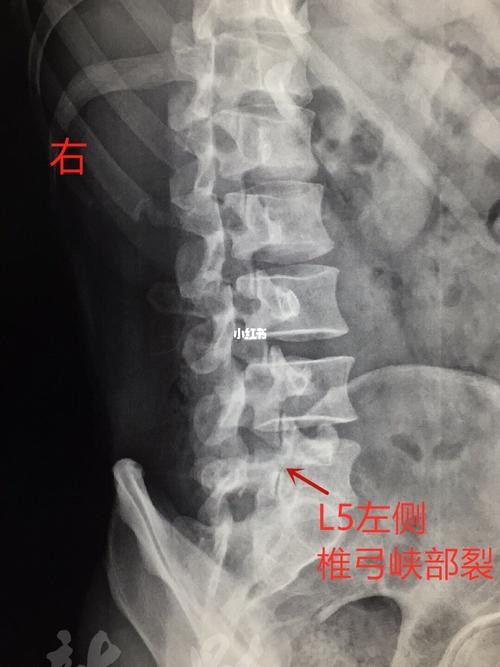

椎弓根断裂

椎弓根断裂,腰椎弓根断裂

腰椎弓根断裂

椎弓根断裂图片

椎弓根骨折

椎弓根峡部

椎弓根峡部解剖